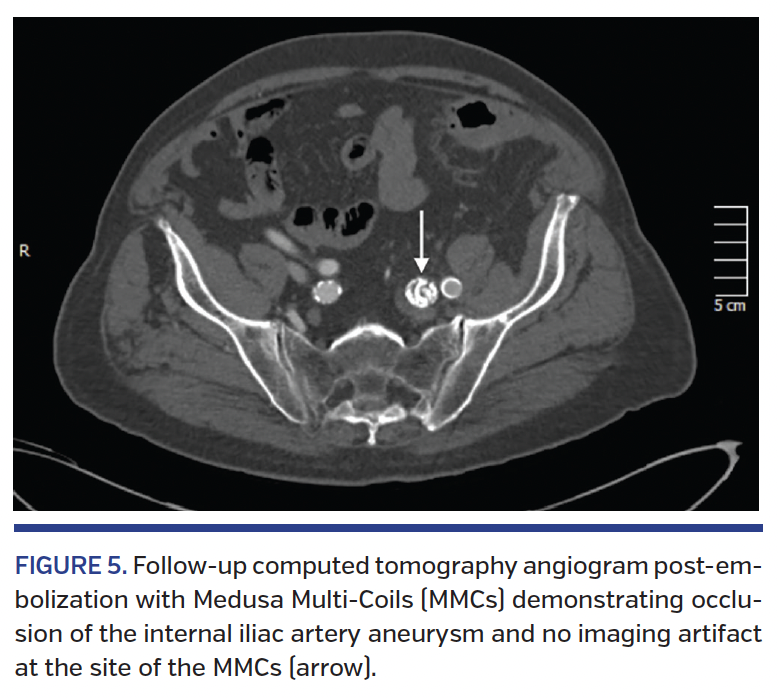

Postembolization CTAs of the 4 cases that returned for follow-up (80%) demonstrated clinically significant occlusion with no contrast filling of the aneurysm (grade D). None of the cases demonstrated any CT imaging artifacts (grade 0) (Figure 5). No further CTA imaging was obtained in these patients following complete occlusion. The last patient in this cohort had not yet returned for the follow-up CT at the time of this data collection.

The metal burden is another concern for follow-up radiographic imaging. Currently, there is no CT or magnetic resonance imaging method that is optimal for follow-up evaluation after endovascular embolization with metal embolic devices due to the metallic artifacts.20 More-invasive imaging procedures such as CTA are often used for evaluation after endovascular treatment, such as in our series. However, these are suboptimal as well due to the required need for radiation exposure and use of contrast agent. In addition, the assessment of aneurysms after metal-coil embolization is hindered by the metal-coil mass, which can obscure neck recanalizations and compaction. In cohort #1, the metal artifacts on the follow-up CTAs were severe (grade 3) in all 3 cases. However, in cohort #2, there were no significant CTA artifacts present in the 4 cases that returned for follow-up. The lack of imaging artifacts offers a more safe and efficacious imaging method for follow-up evaluations after endovascular procedures. This is especially important in elderly populations with many co-morbidities, where procedural time, radiation dose, and contrast agent exposure are more problematic.